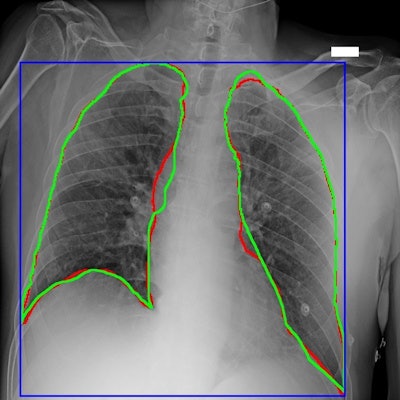

Bracco Imaging and partners in Italy have released a large dataset of chest x-rays from COVID-19 patients to facilitate the development of artificial intelligence (AI) algorithms.

Available with open access to the global scientific community, the AIforCOVID Imaging Archive contains more than 1,000 chest radiographs from COVID-19 patients along with clinical information about the patient. The data was collected as part of the nonprofit AIforCOVID initiative, which was promoted by Bracco in partnership with the Italian Diagnostic Center, according to the vendor.

The vendor noted that the Italian Institute of Technology of Genoa and Campus Bio-Medico University of Rome have also collaborated on data analysis and developing AI algorithms, working in partnership with the Italian Diagnostic Center and Bracco Imaging teams. These models aim to identify indicators of risk for severe disease progression, according to Bracco.